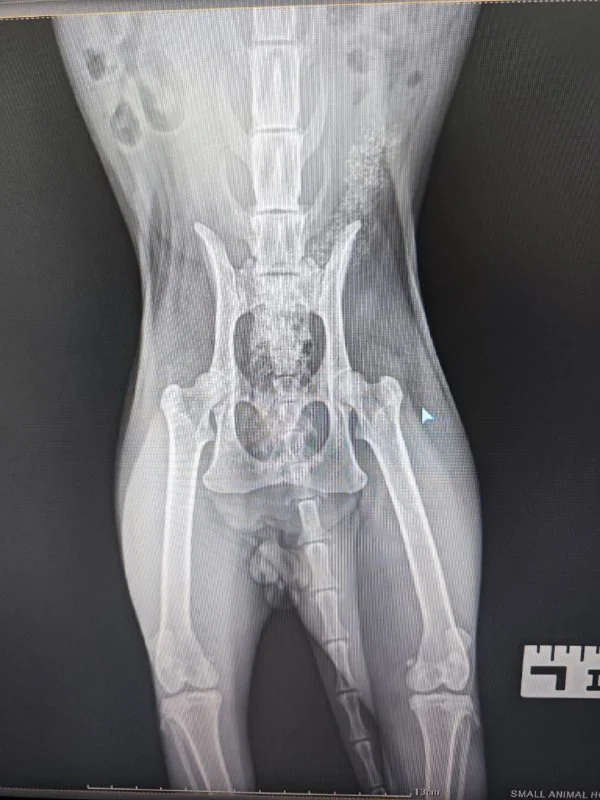

Мы нашли его в парке Дасуди в субботу вечером 06.04, он совершенно не мог ходить, использовал только передние лапы.

Мы смогли отвезти его в клинику, где выяснилось, что перелома нет, есть трещина, которая, скорее всего, повреждает нерв.

По анализам выявили носительство коронавируса.

До 14 апреля включительно он будет на передежке, нам нужна передержка ещё на две недели, чтобы трещина могла зажить (содержание в клетке)

К огромному сожалению из-за своих котов я не смогу оставить Рыжулю у себя на время лечения из-за короновируса, но очень хочется помочь малышу!!

Есть большие шансы того, что ему станет лучше и мы сможем дать ему возможность снова ходить и бегать. Малыш очень ласковый, хороший.